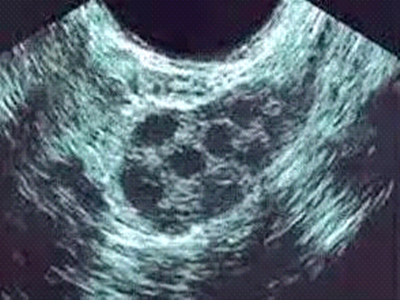

AFC是指卵巢中窦卵泡数,是卵巢的储备功能重要指标之一,反映卵巢中可供产生成熟卵子的“种子”数。通过经阴道B超检查可以了解该指标,双侧卵巢AFC总数小于6-8枚提示卵巢功能减退。B超同时可以测量卵巢的大小,卵巢早衰患者的卵巢体积明显缩小。

(图:B超下显示卵巢AFC)